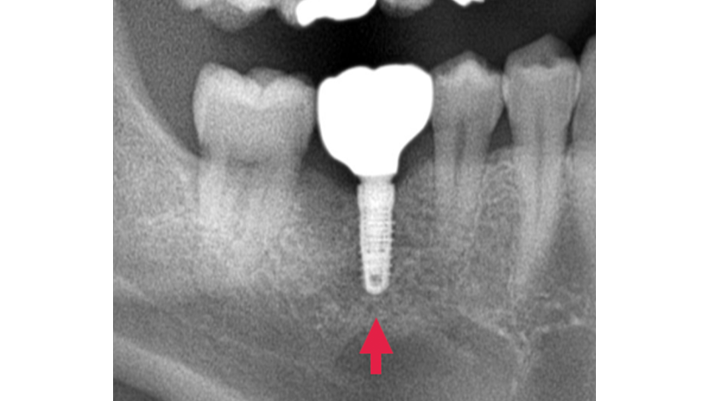

症例4

治療前

治療後

治療の経緯

患者様は「インプラントをするために骨をできるだけ残したい」とのご希望で来院されました。診査の結果、歯根破折により保存は難しく、抜歯が必要な状態でした。また、抜歯後は骨が吸収しやすいリスクが高い状況でした。そのため、抜歯と同時に骨補填材を填入し、メンブレンで保護することで、歯槽堤の形態維持を図り、将来のインプラントに備えた治療を行いました。

同じ症状で悩んでいる方への

メッセージ

歯を抜いた瞬間から骨の吸収は始まります。将来インプラントを検討されている場合は、抜歯時の処置がとても重要です。適切な対応を行うことで、骨の減少を抑え、より良い治療につなげることができます。気になる方は早めにご相談ください。

| 主訴 | 抜歯後のインプラント希望。 |

|---|---|

| 治療期間 | 1回 |

| 治療費 | ¥55,000(税込) |

| 治療内容 | 抜歯後の骨の吸収を防ぐため骨補填材を用いた処置を行いました。 |

| 治療のリスク | 感染や腫れが生じる可能性があります。 |